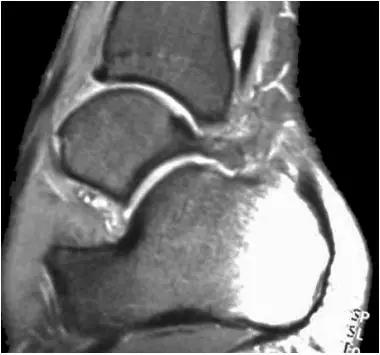

- MRI 检查示距后三角骨及周围软组织有水肿信号,距后三角骨和距骨之间正常的低信号纤维连接中断,出现液性信号。

3、MR表现:

- 三角籽骨或距骨后三角结构模糊和变形,T1WI信号降低, T2WI信号升高,

- 周围脂肪水肿,

- 踇趾长屈肌腱信号升高,见鞘膜积液,

- 胫骨后下跟骨上缘骨结构形态变化和信号异常,

- 三角籽骨和距骨退行性囊变。